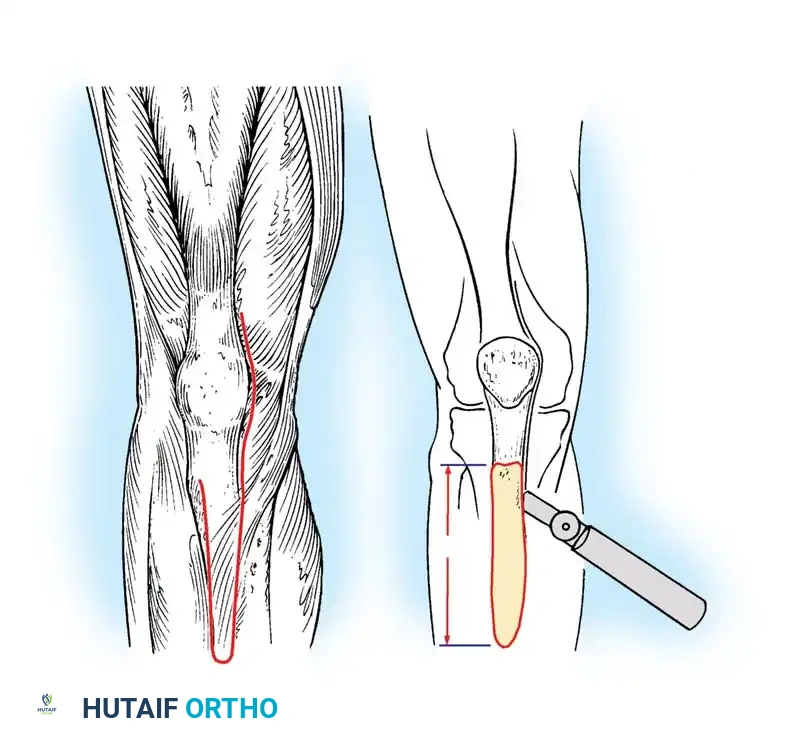

Tibial Tubercle Osteotomy (TTO)

Modified by Whiteside and Ohl, the TTO provides unparalleled exposure of the diaphysis and joint space while relaxing the extensor mechanism.

Fig. 6-77 Tibial tubercle osteotomy to relax quadriceps and improve exposure. An 8- to 10-cm segment is elevated.

An 8- to 10-cm segment of bone including the tubercle and anterior tibial crest is elevated from medial to lateral, leaving the anterior compartment musculature attached laterally to preserve vascularity.

Fig. 6-78 Proximal advancement of tibial tubercle osteotomy for the treatment of patella baja.

The tubercle can be advanced proximally to correct patella baja or joint line elevation. Fixation is achieved with cerclage wires or bicortical screws. Complications include nonunion, proximal migration, and prominent hardware.